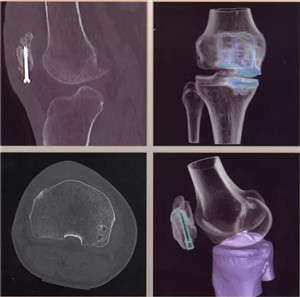

图像分辨超清:0.23毫米的空间分辨率,对于2毫米冠脉支架的细节和支架内再狭窄清晰可辨;可超早期发现微小肿瘤病变。